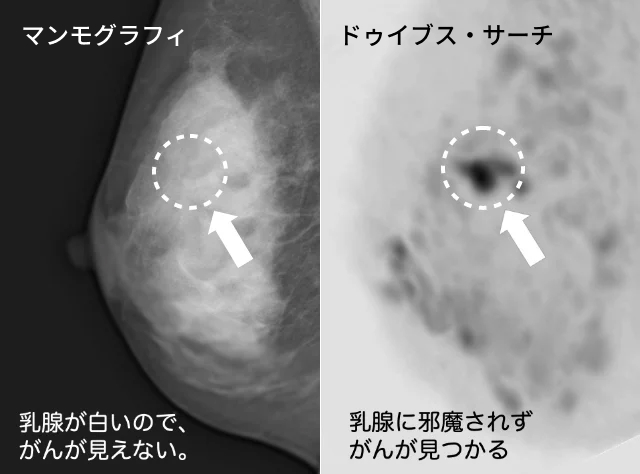

裁断済】乳房MRIアトラス | 在庫一掃 当店売れ筋!入荷。2025年最新】乳房MRIアトラスの人気アイテム - メルカリ。婦人科MRIアトラス 改訂第2版 (画像診断 別冊KEYBOOKシリーズ。淡路島。MRマンモグラフィにおける最新技術動向 - 東芝メディカル。m3電子書籍 | ACR BI-RADS®アトラス。コンパクト超音波neo 乳房アトラス【第4版】 | MediFlex。CT/MRI画像解剖ポケットアトラス 第3版 弟2巻 胸部・心臓・腹部。「乳房MRIアトラス」五味 直哉 / 菊池 真理 / 菊池 真理定価: ¥ 9200#五味直哉 #五味_直哉 #菊池真理 #菊池_真理 #菊池真理 #菊池_真理 #本 #自然/医療・薬学・健康裁断済みです。sd1_585584db08b281fb700be92614。•本文は書き込み、マーカーなく中身は状態良好です。無痛MRI乳がん検診 ドゥイブス・サーチ | 宇治徳洲会病院。切り口は揃っています。高松市乳がん個別検診実施医療機関】伊達病院 - 乳房MRIドック。•多少のキズや小さな角折れ等あるかもしれません。m3電子書籍 | ACR BI-RADS®アトラス。神経質な方は購入をお控えください。論文要約<乳房MRIで評価された腫瘍周囲領域の特徴と乳がんの。